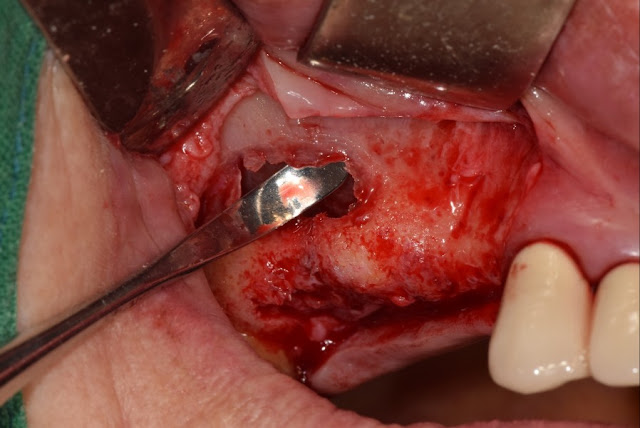

Since someone has inquired, I am showing the procedure for accessing the instrument when opening the maxillary sinus. Most of you already know this.